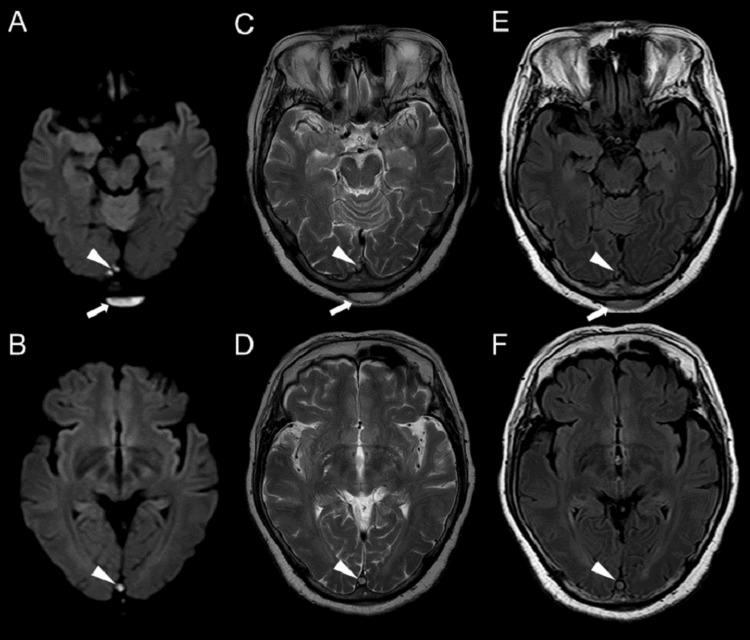

Infectious cerebral venous sinus thrombosis (CVST) typically arises from contiguous infections such as sinusitis or otitis media; however, CVST secondary to a subcutaneous abscess is exceedingly rare. We report the case of a 68-year-old woman who presented with a fever, headache, and a painful occipital scalp mass. Initial imaging identified a subcutaneous abscess in the occipital region, and subsequent magnetic resonance imaging (MRI) revealed thrombosis involving the superior sagittal, transverse, and sigmoid sinuses. Methicillin-sensitive Staphylococcus aureus (MSSA) was isolated from both blood and abscess cultures. Anticoagulation and intravenous antibiotic therapy were promptly initiated. Diplopia developed on day 10 of illness, was closely monitored through serial neurological examinations, and gradually resolved over the ensuing months, with complete resolution noted at the six-month follow-up. Follow-up imaging at 24 months demonstrated partial recanalization of the affected venous sinuses. This case underscores a rare but critical progression from a localized scalp infection to CVST. Clinicians should maintain a high index of suspicion in patients presenting with occipital scalp infections accompanied by neurological symptoms. To our knowledge, this is one of the few reported cases of CVST arising from a posterior scalp abscess, expanding the spectrum of infectious sources and guiding management strategies in similar presentations.